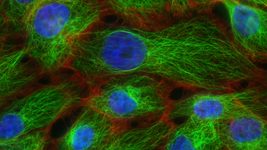

Компанія OpenAI створила модель, яка створює білки, здатні перетворювати звичайні клітини на стовбурові. Чи зможе вона омолоджувати?

Компанія OpenAI створила модель, яка створює білки, здатні перетворювати звичайні клітини на стовбурові. Чи зможе вона омолоджувати?